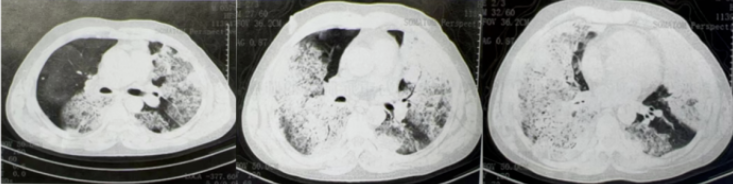

12月8日当地医院胸部CT示:两肺广泛感染(图1)。12月13日我院胸部CT示两肺感染及多发小结节(图2)。

图1 外院胸部CT